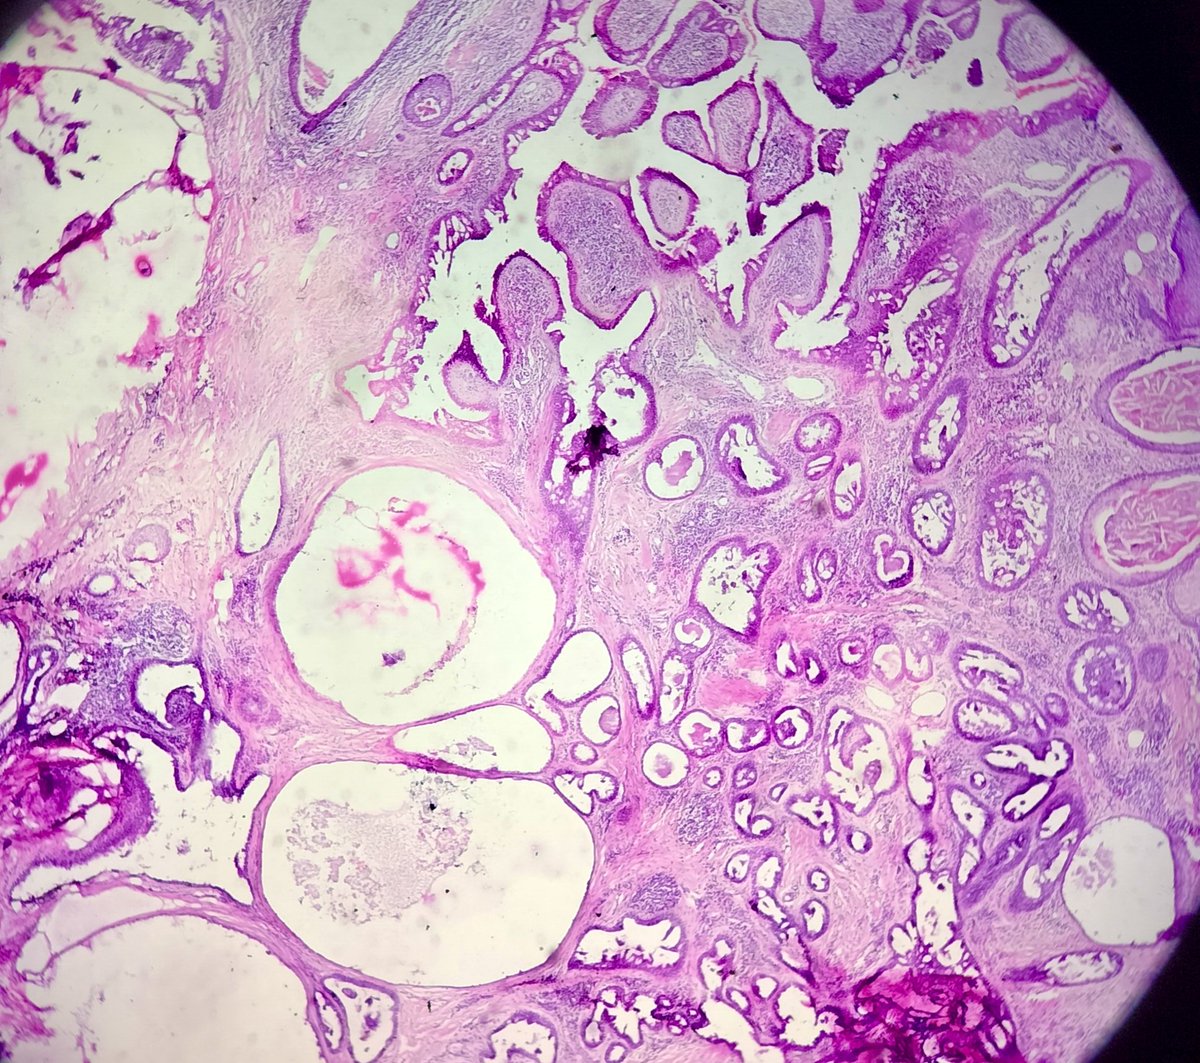

🔬Diagnosis & Annotated Pearls with DDx | Previous Case! ➤ DENTIGEROUS CYST #Pathresidents #PathTwitter #pathx @Pathologists #HandNpath @Pathology_mcqs @AceMyPath

A 35 Yr | 👨 "Cyst Chronicles: Secrets of the premolar prison" ● Right Mandible 🎯 Shoot your 2 most favored DDx's @Pathologists #PathTwitter #pathX #pathresidents #HeadandNeckPath